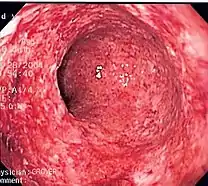

Colitis (inflammation of the colon) caused by Crohn's Disease.